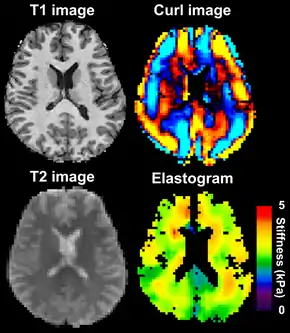

Magnetic resonance elastography of the brain. A T1 weighted anatomical image is shown in the top-left, and the corresponding T2 weighted image from the MRE data is shown in the bottom-left. The wave image used to make the elastogram is shown in the top-right, and the resulting elastogram is in the bottom-right.

MRE of the brain [27] was first presented in the early 2000s.[28][29] Elastogram measures have been correlated with memory tasks,[30] fitness measures,[31] and progression of various neurodegenerative conditions.[27] For example, regional and global decreases in brain viscoelasticity have been observed in Alzheimer’s disease[32][33] and multiple sclerosis.[34][35] It has been found that as the brain ages, it loses its viscoelastic integrity due to degeneration of neurons and oligodendrocytes.[36][37] A recent study looked into both the isotropic and anisotropic stiffness in brain and found a correlation between the two and with age, particularly in gray matter.[38]